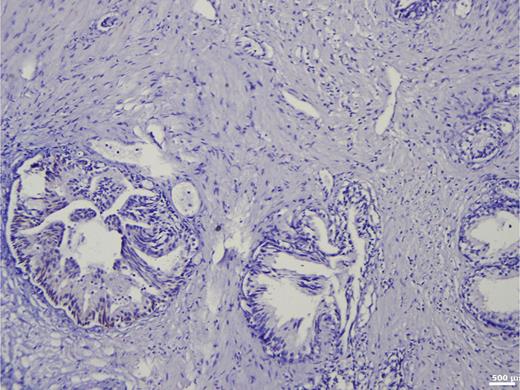

The average BSP expression in the metastatic group was 55.5%, while in the nonmetastatic group, it was 25.7%. This difference was statistically significant (Z = −9.429; pU < 0.001, Table 4). Notably, all patients in the metastatic group had a BSP value of at least 20%, whereas in the nonmetastatic group, 23.8% (135/567) had BSP values between 0 and 5%, and 43.7% (248/567) had BSP values below 20% (Fig. 3). In the entire patient cohort, the BSP expression patterns were the following:

23.8% were BSP-negative (0–5% expression).

22.2% had high BSP expression (>40%).

82.9% of metastatic patients exhibited BSP expression of at least 40%.

No metastatic patient had BSP values below 20%.